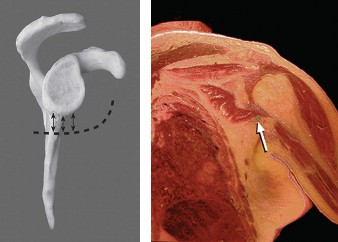

The correct answer is (C). This structure is a thickening of the coracohumeral ligament that starts anteriorly just posterior to the short head of the biceps tendon on the coracoid process, extends posteriorly through the edge of the avascular zone of the supraspinatus and infraspinatus, and ends at the inferior edge of the infraspinatus. One proposed function of the cable is to act like a cable in a suspension bridge, helping to evenly distribute forces on the humeral head produced by the rotator cuff (see Fig. 2–6).

Figure 2–6_Illustration showing the rotator cable and rotator crescent. B, rotator crescent; C, rotator cable; BT, biceps tendon; I, infraspinatus; S, supraspinatus; TM, teres minor. (Redrawn from Burkhart SS, Lo IKY. Arthroscopic rotator cuff repair. _J Am Acad Orthop Surg. 2006;14(6):333–346.)

The rotator crescent (Answer A) is the thin tissue that exists lateral to the rotator cable medial to the attachment of the supraspinatus and infraspinatus. It is composed on the tendons of these two rotator cuff muscles (see Fig. 2–6).